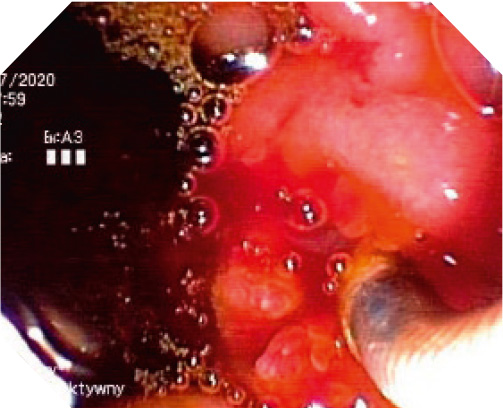

Case Presentation 2

I also suggest the use of BMCL stents in patients in whom it would be very difficult to reach the Vater’s papilla area, due to the high dynamics of the neoplastic process. For example, a 35-year-old patient with inoperable biliary tract tumor and a clogged duodenum due to NPL infiltration, with plastic stents used previously, theoretically without any possibility of replacing them with new ones.

7. Clogged plastic stents and visible implanted duodenal stent (first stage of the procedure).

In the first stage, a duodenum stent was placed. A week after the duodenal stent was placed, the descending part and the papilla region were reached through the duodenal stent and a BMCL stent was placed into the biliary tract. The cross-over biliary and duodenal stents enable the correct drainage of the bile and the movement of food content into the digestive tract.